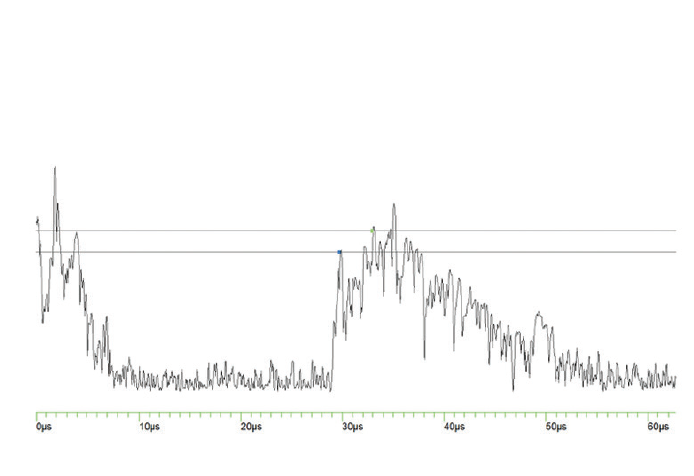

When the patient presented for his ocular oncology appointment, he had not developed any discomfort or pain in his eyes since his appointment with a referring physician that week. His VA was 20/100-1 OD and 20/60+2 in his left eye (OS). Posterior segment evaluation OD was significant for an elevated mass temporal to the macula, 4.5 by 8.0 disc diameters in size. Fundus photography of the lesion highlighted its orange color and size (Figure 1). Fluorescein angiography showed the mass infratemporal to the macula (Figure 2). Ocular ultrasound revealed an elevated posterior pole mass, 12 mm by 14 mm in size, with high internal reflectivity (Figure 3). Ultrasound A-scan demonstrated an area of increased reflectivity (Figure 4). The presumed diagnosis was choroidal metastasis from the patient’s active thyroid cancer.

Figure 4. A-scan reveals an area of increased reflectivity.